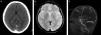

Finalmente, incluimos en este apartado a los hematomas intraparenquimatosos (HIP). Estos presentan cefalea seguida o no de déficits focales, según sea su localización. Si bien generalmente se originan por hipertensión arterial, otras causas menos frecuentes pueden ser el consumo de cocaína, la angiopatía amiloide, las coagulopatías, las malformaciones vasculares y los tumores. Con fines didácticos mostramos un caso de HIP en una paciente con lupus y síndrome de moyamoya9 (fig. 9).

Paciente con cefalea y hematoma en la región tálamo capsular derecha. Se observa (a) en la TC una lesión espontáneamente densa (flecha) y (b) en la secuencia GRE, corte axial, un área de hipointensidad (flecha). (c) La angio-RM tridimensional TOF registra ausencia de señal en los tramos terminales de ambas carótidas internas (puntas de flecha), mientras que (d) en los cortes axiales crudos se identifican pequeños vasos colaterales en las arterias comunicantes posteriores y en ambas arterias cerebrales posteriores, hallazgos correspondientes a enfermedad de moyamoya en estadio III (flechas).